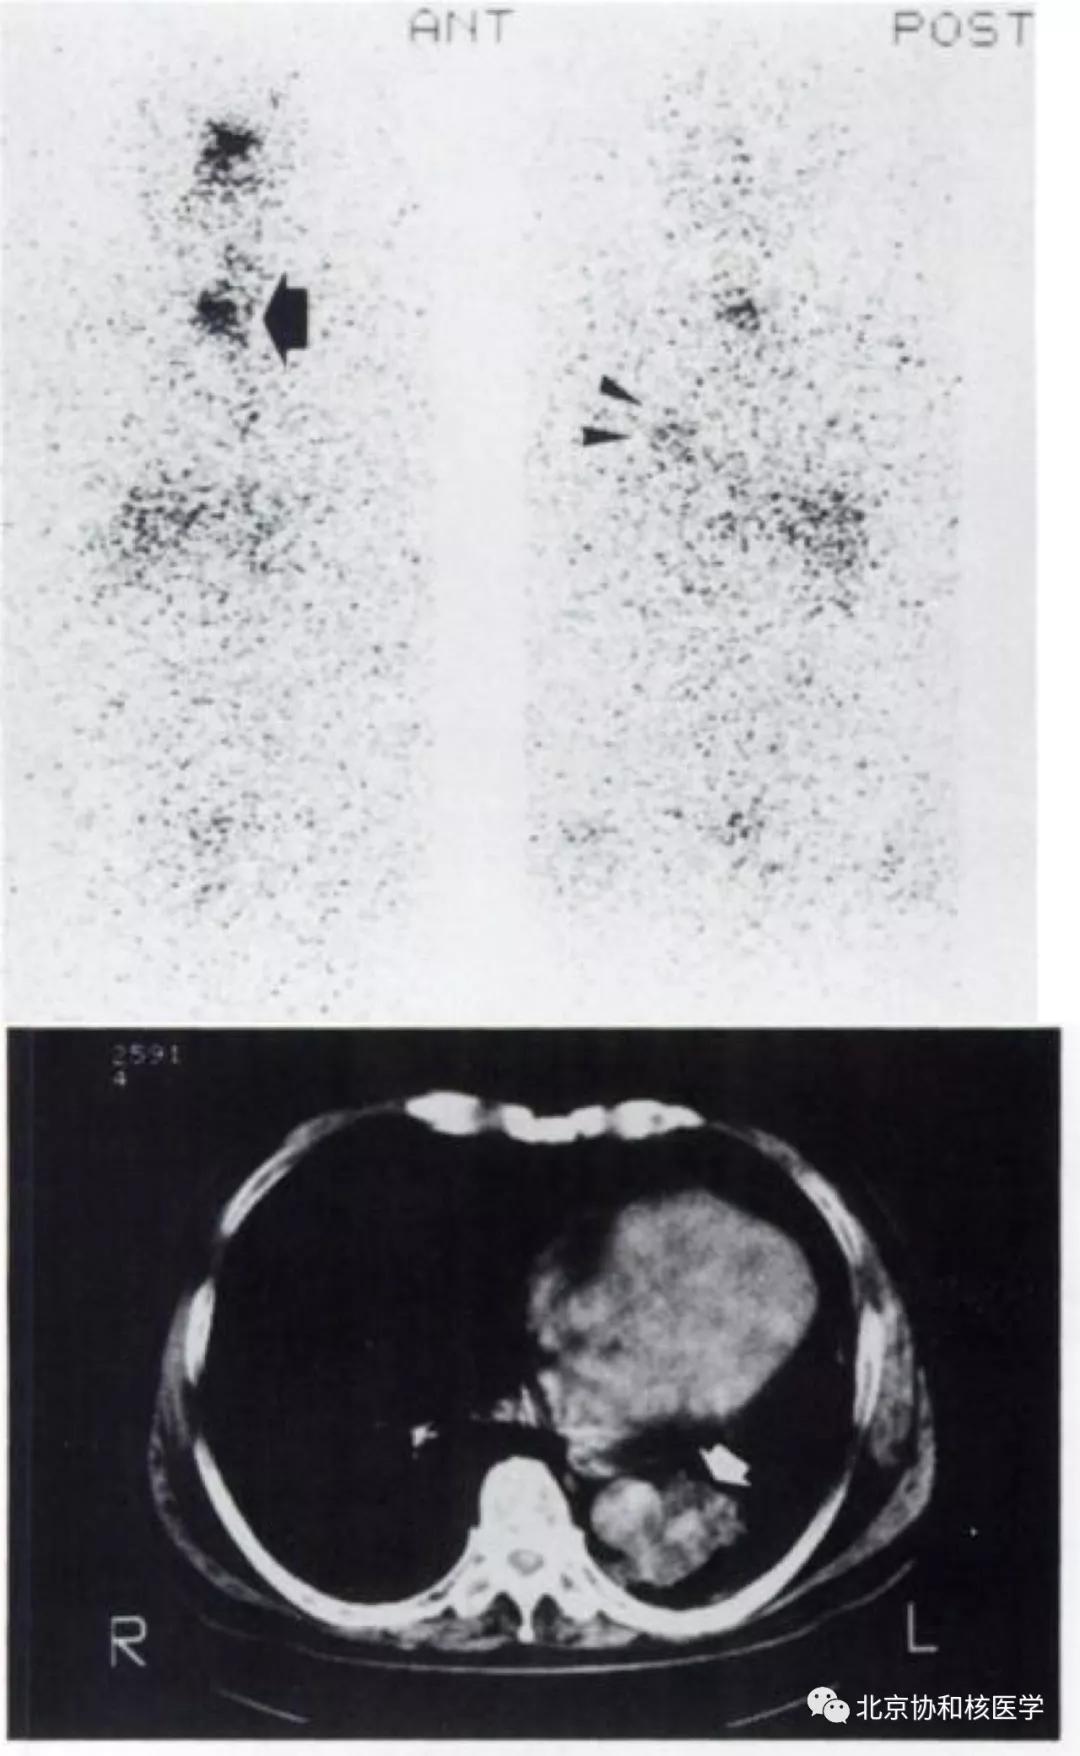

肺鳞癌所致碘摄取(后位图像),同时可见颈部甲状腺残余病灶: